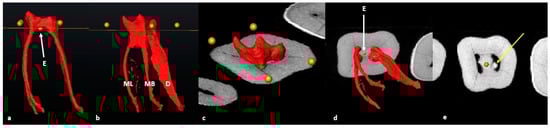

3.2. Mandibular First Molars: Three Rooted

3.3. Maxillary First Molars: Three Separate Roots

3.4. Maxillary Molars: Variants in Mesial or Distal Bifurcations